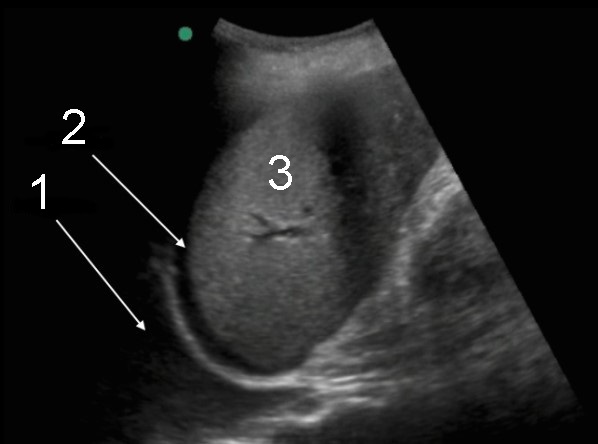

Thoracentesis Pleural Effusion and Ascites Image

Left Pleural Fluid

Free Fluid

Spleen